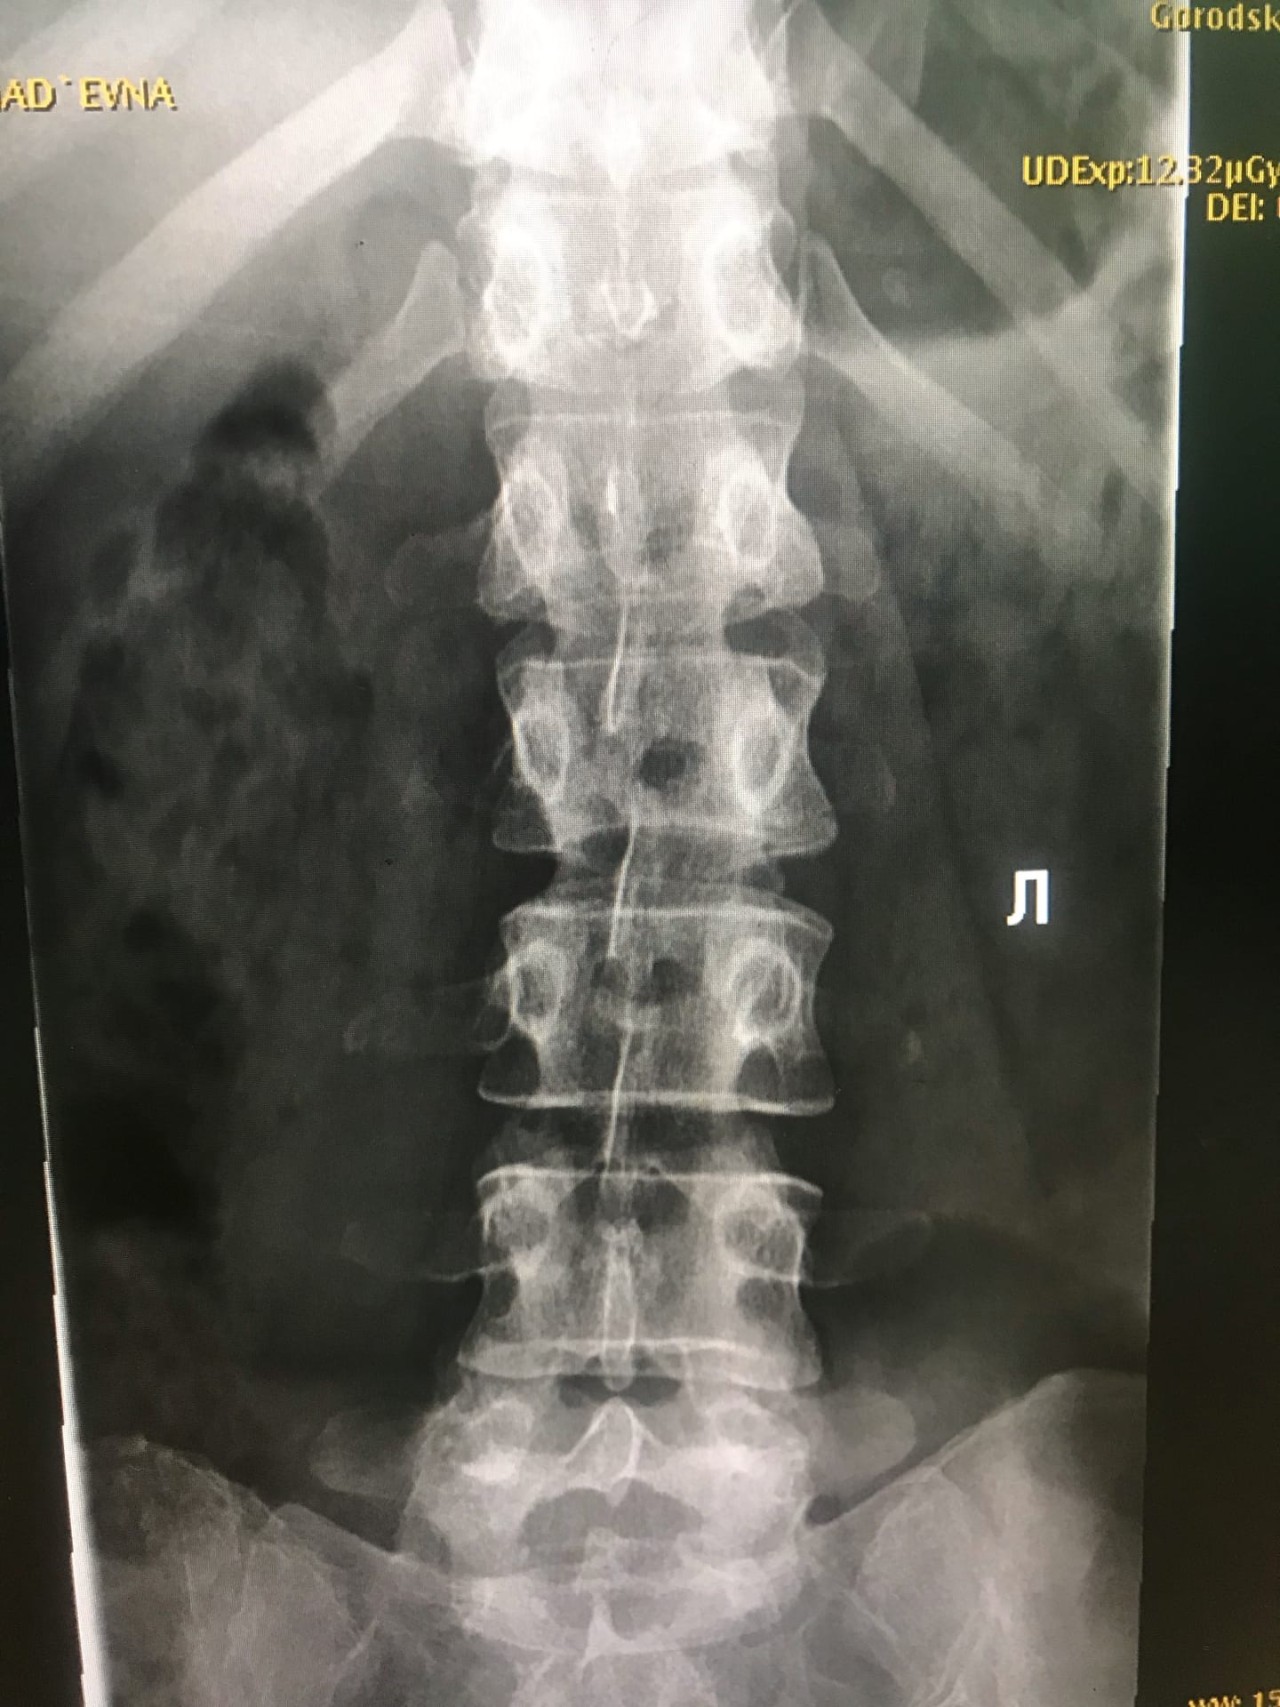

Рентген поясницы: анатомические особенности и медицинские исследования

Раздел: Фотоэссе